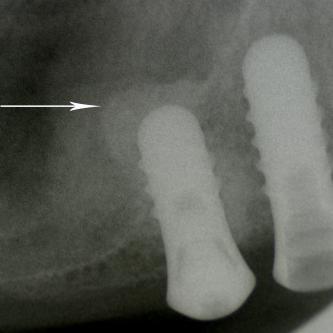

Exemple 7: Un implant au niveau de la deuxième prémolaire inférieure gauche.

Exemple 7: Le moignon vissé sur l'implant.